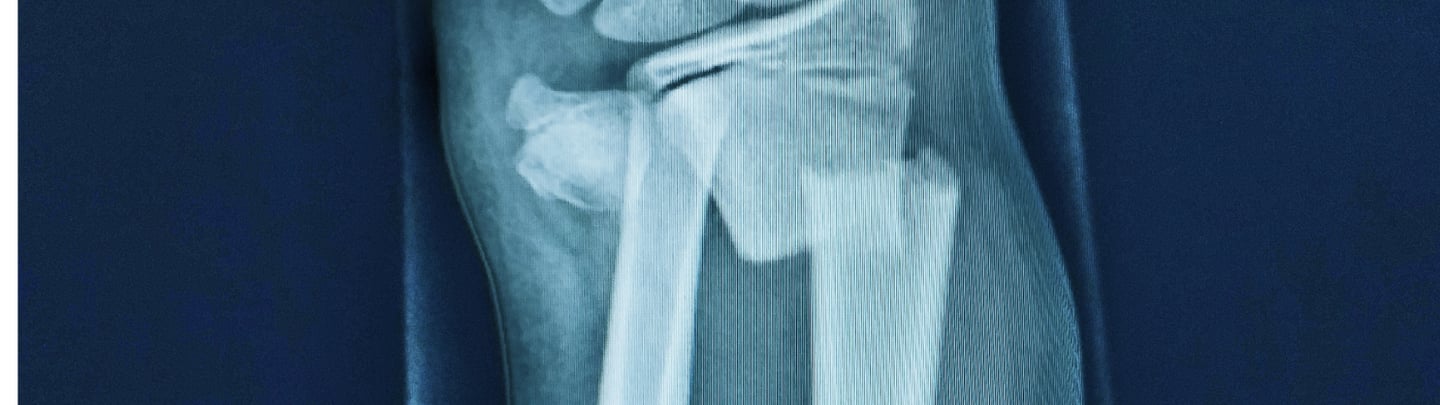

Colles fractures are among the most common wrist injuries, especially in high-impact situations like motorbike accidents and cycling accidents. The injury typically occurs when a person instinctively throws out their hand to break a fall. The force drives the wrist backwards, causing a break in the radius bone near the wrist joint.

Immediately after the injury, most people feel a sharp, intense pain in the wrist, often accompanied by swelling, bruising, and an obvious deformity. The wrist may look bent or twisted unnaturally. Movement becomes very limited, and any pressure on the area can be excruciating.

Colles fractures often require realignment of the bone (reduction), and in many cases, immobilisation in a cast or even surgery. Leaving the fracture untreated or delaying care can lead to long-term problems like misalignment, reduced mobility, or nerve damage. Early treatment gives the best chance for a full recovery.

Treatment depends on the severity of the fracture. Milder cases may be treated with a plaster cast for 6–8 weeks. More complex breaks may require surgical fixation with metal pins, plates, or screws.